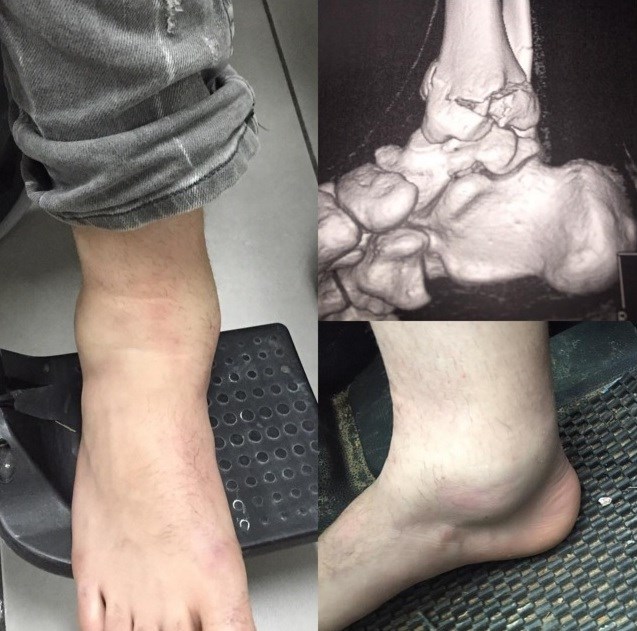

Ο Jack Miller είναι αμφίβολος για το τεστ της Μαλαισίας που θα ξεκινήσει την 1η Φεβρουαρίου, μιας και ο Αυστραλός άσος έσπασε το δεξί του πόδι κάνοντας motocross.

Ο νέος αναβάτης της Marc VDS προπονούνταν στο Bellpuig της Ισπανίας όταν εξαιτίας πτώσης του την Κυριακή που μας πέρασε, έσπασε το πόδι του.

Χτες το πρωί ο Miller μπήκε στο χειρουργείο και θα παραμείνει υπό παρακολούθηση στο Πανεπιστημιακό Νοσοκομείο της Βαρκελώνης για τις πρώτες 48 ώρες.